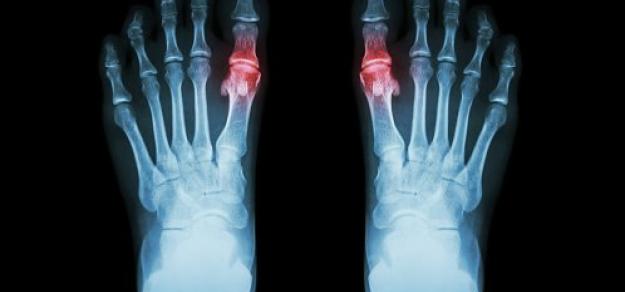

Hiperuricemia y tratamiento farmacológico de la gota

Butlletí d’informació terapèutica BIT. Vol. 30, núm. 2, 2019CatSalut, 10 de mayo de 2019Este Boletín revisa los tratamientos farmacológicos de los ataques agudos de gota y de la hiperuricemia haciendo un posicionamiento de los fármacos disponibles. Finalmente, se abordan diferentes controversias relacionadas con el tratamiento como el manejo de la hiperuricemia asintomática o la retirada del alopurinol.